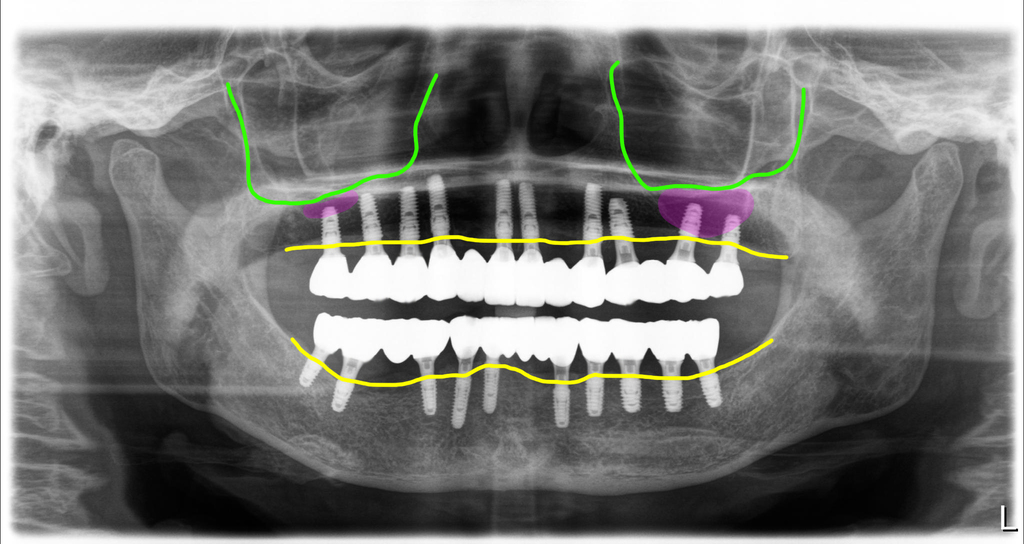

브릿지 타입으로 지르코니아에 맞춤지대주 세멘트 방식으로 치료를 했으며, 구치부는 나사구멍을 형성해서 이후 보수에 유리하도록 디자인했습니다.

그리고 치아와 치아 사이에 공간을 두어 치간치솔로 위생적으로 관리할 수 있도록 디자인했습니다.

4회 내원 치료기간 6개월 전체임플란트 치료완료

상악동 뼈이식도 있고, 골밀도도 낮았지만 수술을 한번에 끝냈고, 수술당일 임시치아도 적용할 수 있어서 비교적 양호하게 치료가 진행되었던 환자입니다.

환자분이 아주 꼼꼼하신 분이어서 치료후에도 관리를 아주 잘 하고 계십니다. 간혹 임플란트 치료후 입에서 냄새가 나지 않을까? 걱정하는 댓글들을 읽게 되는데요. 제가 하는 방식으로 치아를 만들고 환자가 기본적인 관리만 하면 입에서 냄새날 일은 없습니다.